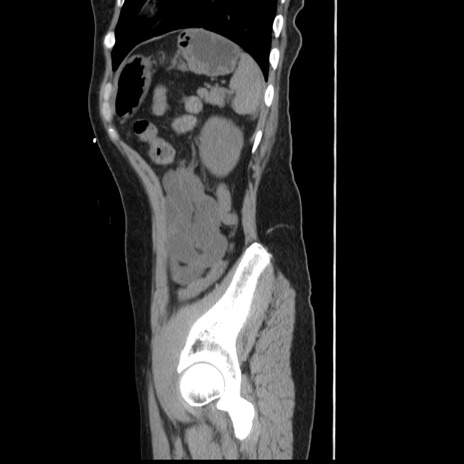

冠状断像

【症例】 50歳代女性

【主訴】 腹痛

【現病歴】前日生レバーを食べた。今朝に排便あり。 昼前に突然発症の腹痛を生じ、当院救急外来を受診した。

【既往歴】 子宮筋腫にてで子宮全摘後

【身体所見】 意識清明、腹部:平坦、軟、下腹部やや左を中心に圧痛・反跳痛あり、筋性防御あり

【データ】WBC 7800、CRP 0.07